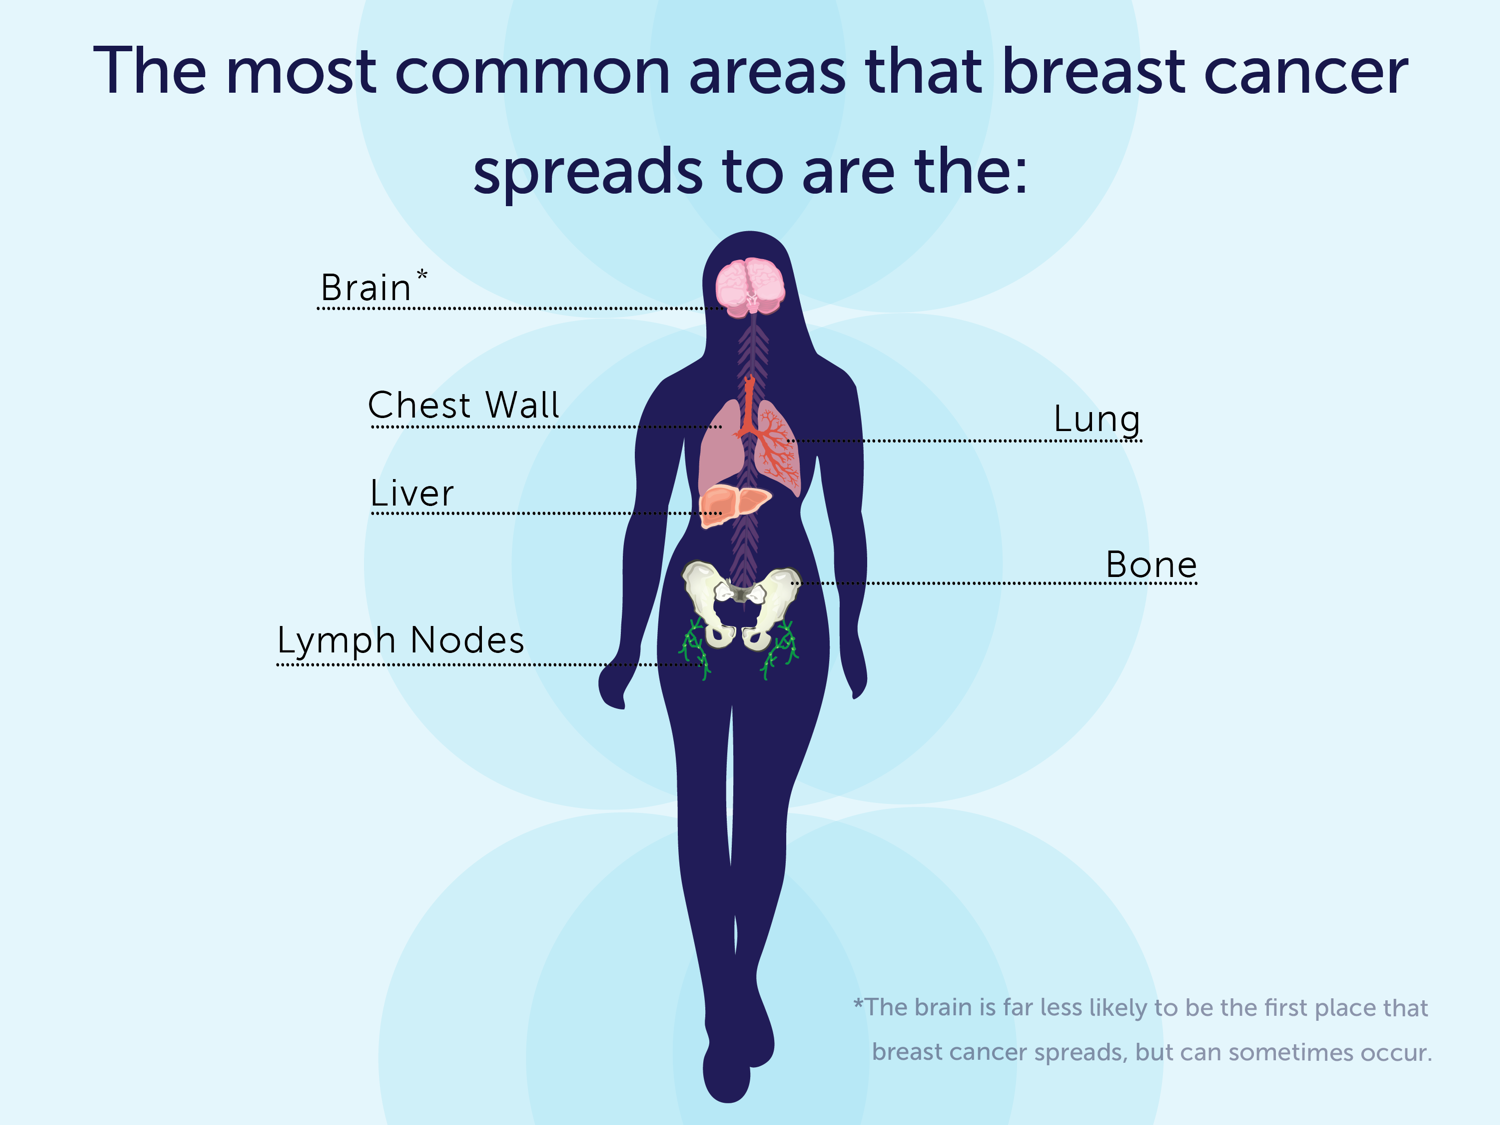

What Are The Symptoms Of Metastatic Breast Cancer?

cancer breast metastatic symptoms lymph bone lung common nodes brain spreads chest wall first most liver areas place occur

What are the symptoms of metastatic breast cancer?. Breast ultrasound right hypoechoic mass enhancement lobulated showing circumscribed well examination margins internal echogenicity open acoustic figure posterior shadowing lesions. What is a clear margin in breast conserving cancer surgery?